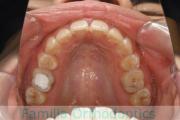

No.23V-132

- 主な症状:

- 開咬

- 年齢:

- 16歳

- 性別:

- 男性

- 抜歯部位

- 上:

- 88

- 下:

- 主な使用装置:

- FEA

- 治療にかかった費用:

- 87万円

開咬なので治療したいとのことで来院されました。受け口傾向のある開咬(前歯が咬み合わない)でしたので、下の親知らずを抜歯してマルチブラケット法にて治療を行いました。約1年半、20回程度の通院が必要でした。開咬は舌の癖の影響が強く、後戻りのリスクが高いケースといえます。